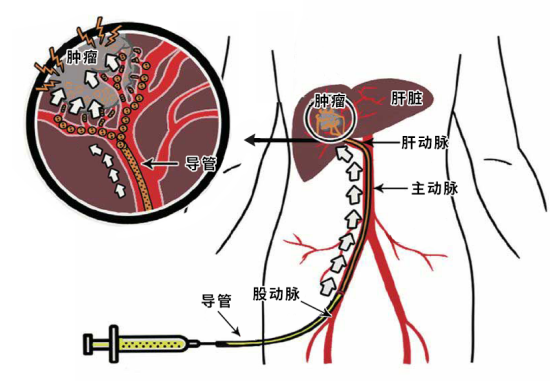

ولكن عندما أخبره الطبيب المعالج ، أن العلاج التدخلي ضروري، رفض العم وانج دون تفكير ثانٍ. "لقد تسبب العلاج التدخلي السابق في آلام شديدة." كان العم وانغ خائفًا من تجربة هذا النوع من الألم مرة أخرى ولم يجرؤ على تجربته بسهولة. بعد توجيهات الدكتور وشرحه الدقيق، قرر العم وانج أن يجرب الأمر مرة أخرى وخضع في النهاية للعلاج الكيميائي عن طريق الشريان الكبدي + الانسداد الكيميائي الفائق الانتقائي للشريان الكبدي العلوي الأيمن + قسطرة الشريان الكبدي تحت التخدير الموضعي. تمت العملية برمتها تحت إشراف DSA.

تحت التخدير الموضعي، يقوم الطبيب التداخلي بثقب الفخذ (الشريان الفخذي) وإدخال قسطرة رفيعة يتم إرسالها بشكل انتقائي على طول الأوعية الدموية إلى شريان إمداد الدم للورم ويحقن أدوية العلاج الكيميائي والجسيمات الانسدادية، والتي يمكن أن "تسمم" خلايا الورم و"تقطع إمداد الورم بالغذاء" (تسد إمداد الدم)، مما يؤدي في النهاية إلى نخر الورم بسبب التأثيرات المزدوجة لنقص التروية وتركيزات الدواء العالية. وبعد ذلك، تم وضع طرف القسطرة الدقيقة في الشريان الكبدي لتسهيل استمرار ضخ أدوية العلاج الكيميائي بعد العودة إلى الجناح.

△الصورة من الانترنت

وهذا لا يتغلب فقط على مشاكل التخفيف النظامي لتركيز دواء العلاج الكيميائي و"تأثير الإزالة الأولية" للأدوية في الكبد الناجمة عن العلاج الكيميائي النظامي الوريدي المحيطي التقليدي (في إشارة إلى الظاهرة التي يتم فيها إعطاء بعض الأدوية عبر الجهاز الهضمي واستقلابها في الغشاء المخاطي المعوي والكبد قبل امتصاصها في الدورة الدموية، مما يؤدي إلى انخفاض في كمية الدواء غير المتغير الذي يدخل الدورة الدموية)، ولكنه يقلل أيضًا من الآثار الجانبية لقمع نخاع العظم وردود الفعل المعدية المعوية الناجمة عن العلاج الكيميائي النظامي. يتميز بأنه أقل صدمة، ووقت علاج أقصر، وتعافي أسرع، وإمكانية تكرار قوية.